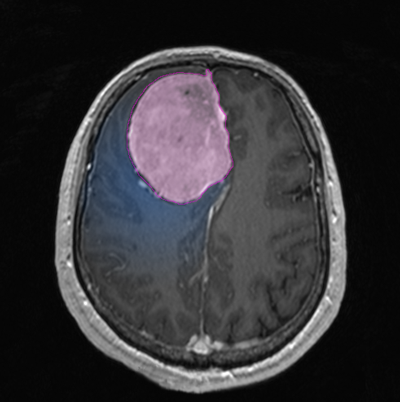

Διάγνωση Απαραίτητα είναι: Η λεπτομερής λήψη ιστορικού και η κλινική εξέταση, Η μαγνητική τομογραφία του εγκεφάλου με σκιαγραφικό, Σε ορισμένες περιπτώσεις: Η μαγνητική αγγειογραφία ή/και φλεβογραφία του εγκεφάλου, Η μαγνητική τομογραφία του εγκεφάλου με σκιαγραφικό για νευροπλοήγηση, Ηλεκτροεγκεφαλογράφημα και άλλες εξειδικευμένες εξετάσεις όπως μέτρηση οπτικής οξύτητας και οπτικών πεδίων προτείνονται κατά περίπτωση. |